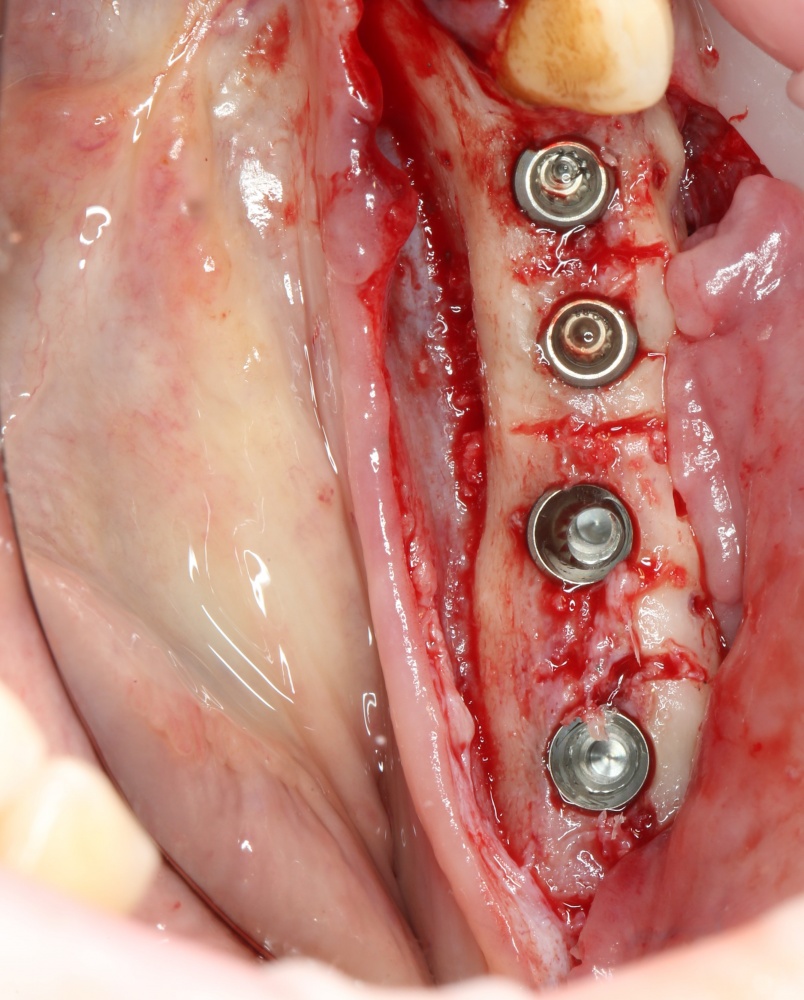

Рекомендации по установке имплантов. Для всех. Часть V.